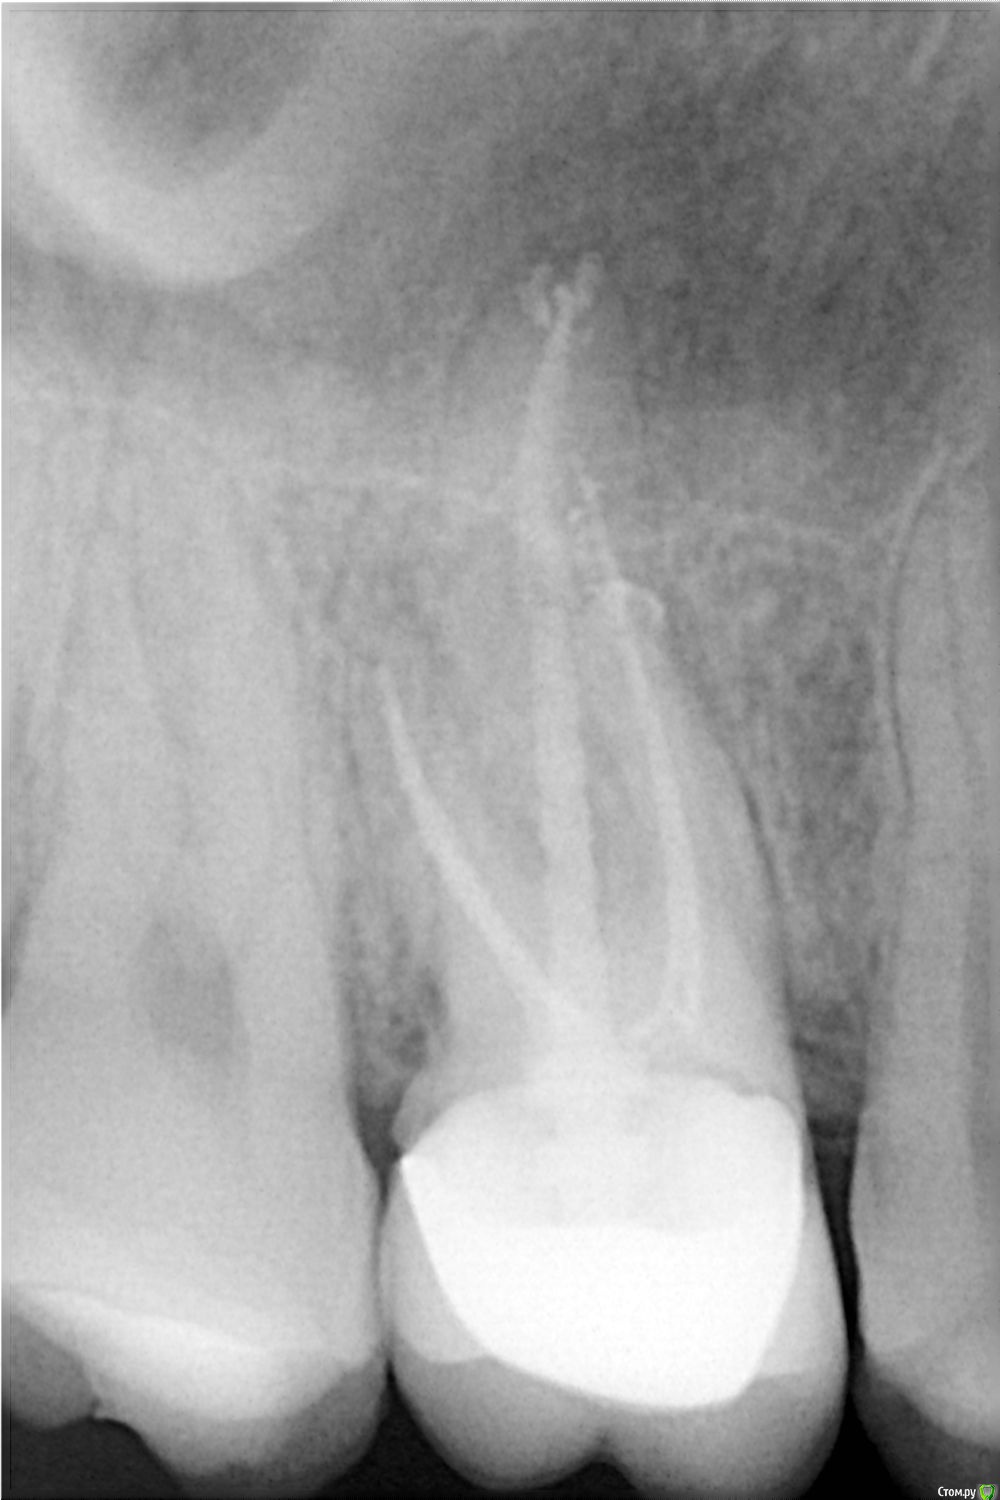

Здравствуйте! На шестом верхнем зубе мне запломбировали каналы и установили коронку. Через два дня, как ее установили, при жевании появились болевые ощущения. Сам по себе зуб не болит. Через неделю боль прошла. Я сделала снимок. ПРОШУ ОЦЕНИТЬ СОСТОЯНИЕ ЗДОРОВЬЯ ДАННОГО ЗУБА! post-48914-0-22677500-1472976638_thumb.jpg

Маленькая предыстория: через пару дней после установки штифта в шестой зуб возникла боль при жевании в седьмом зубе, находящемся рядом с шестым. По ощущениям боль была именно не в зубе, а в кости и локализовалась с одной стороны, которая ближе к шестому зубу, в котором установлен штифт. Через неделю боль стихла. Врач сказала что это была нагрузка по прикусу, т.к. коронки еще нет. Но у меня есть сомнения... И зуб на снимке сейчас выглядит иначе, после пломбировки каналов, на конце самого длинного канала был маленький шарик пломбировачного материала, а сейчас там все по другому. Скажите пожалуйста что с ним на самом деле? post-48914-0-22677500-1472976638_thumb.jpg